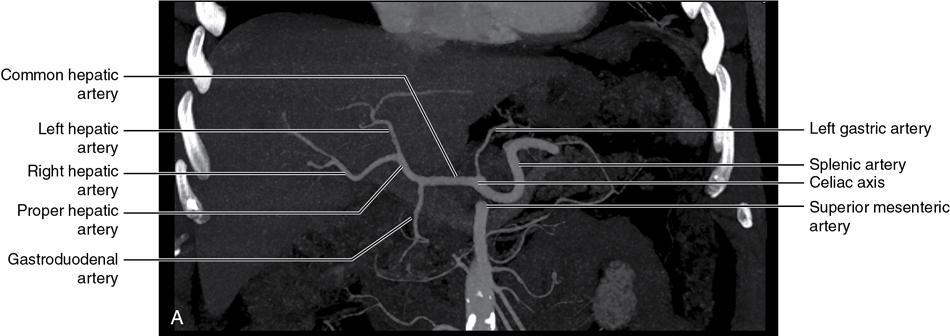

CROSS SECTIONAL ANATOMY OF ABDOMEN Satya Jha NORMAL ANATOMY OF ABDOMEN AND PELVIS Amandeep Singh The two major surfaces: The anterior and posterior layers of the coronary ligament converge on bare area (not covered by peritoneum). Its right and left margins form the right and left triangular ligaments. The right triangular ligament extends toward the diaphragm and separates right subphrenic space from right subhepatic space. The left triangular ligament gives tracts extending to the diaphragm and falciform ligament and does not compartmentalize the left subphrenic space. Ligamentum teres or the obliterated umblical vein is contained in falciform ligament which attaches the liver to anterior abdominal wall. The main portal vein, the proper hepatic artery and the common bile duct are contained within investing peritoneal folds of hepatoduodenal ligament at the porta hepatis (Fig. 7.2.2.1). Liver is divided into eight segments which are functionally independent and have their own vascular supply and biliary drainage. Arterial circulation: The branches of the hepatic artery accompanying the portal veins. Hepatic venous system: The right, middle, and left hepatic veins draining into IVC (Figs. 7.2.2.2 and 7.2.2.3). The gallbladder is a blind pear-shaped muscular membranous sac which is an embryologic derivative of the foregut, is a pouch lying along the undersurface of the liver. The gallbladder fossa is located in the plane of the interlobar fissure, which lies between the right and left hepatic lobes. Its major function is to store and concentrate bile which is produced by the liver. It measures approximately 4 cm in diameter when it is normally distended. Gallbladder is a smaller tubular structure in contracted state. The normal gallbladder wall thickness ranges from 1 to 3 mm. The gallbladder is divided into the fundus, body and neck. Infundibulum is present in the region of neck of the gallbladder, which is called the Hartmann pouch, where gallstones are usually impacted. Intrahepatic biliary radicles (IHBRs) scattered throughout the liver get confluent towards the hilum. They unite to form the right and left main hepatic ducts which further unite to form common hepatic duct (CHD) at the hilum. Common bile duct is formed by the union of cystic duct with common hepatic duct. The main pancreatic duct is joined with the common bile duct to form the ampulla of Vater at the major duodenal papilla (Figs. 7.2.2.4 and 7.2.2.5). Pancreas is located in anterior pararenal space of retroperitoneum anterior to perirenal (Gerota’s) fascia and posterior to parietal peritoneum. It is divided into head, uncinate process, neck, body and tail from right to left. Pancreas lies anterior to portal vein, which marks the point of transition between the body and neck. The region between head of pancreas and second and third parts of duodenum is known as the pancreatic groove. In postnephrectomy cases or with agenesis of kidney or ectopic kidney, pancreas moves posteriorly to partially fill in the empty renal fossa; its soft tissue density should not be mistaken for recurrent tumour. It is located in the pancreatic groove and is bounded superiorly by the duodenal bulb, laterally by second portion of duodenum, inferiorly by third portion of duodenum, medially by superior mesenteric vein and anterior to inferior vena cava. It is a wedge or wedge shaped lying posterior to superior mesenteric artery and vein. It is an imaginary junction between the head and body and lies directly over the junction of the splenic vein and superior mesenteric vein. It is located posterior to the lesser sac and anterior to the aorta, left adrenal gland, left kidney, and renal vessels and runs obliquely upward to the left of the superior mesenteric vessels. It is situated median to the colonic flexure and anterior to the left kidney. It is located in close proximity to the splenic hilum without a notable relation with the body of pancreas. It is seen anterior to the left kidney and median to the colonic flexure. The distal part of the tail passes between the peritoneal layers of the splenorenal ligament (Fig. 7.2.2.6 and 7.2.2.7).